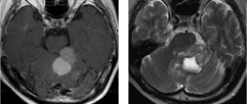

症例 3

乳癌による転移性小脳腫瘍に対して開頭腫瘍摘出術を施行しました。ダンベル状の多発病変でしたが、一期的に摘出しました。術後放射線治療を行いました。